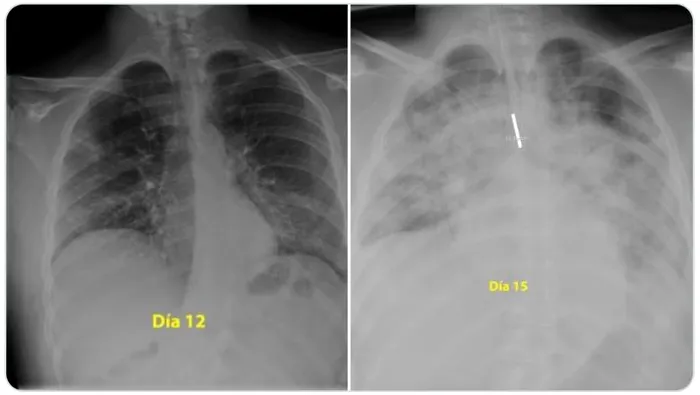

Un renumit medic pneumolog din Spania a făcut publice pe rețeaua de socializare Twitter două radiografii care arată cum a acționat noul coronavirus asupra plămânilor unui tânăr de 28 de ani. Pacientul a suferit o formă gravă de Covid-19, iar în numai trei zile virusul SARS-CoV-2 i-a „mâncat” ambii plămâni!

„Pentru cei care cred că sunt nemuritori și continuă să iasă în parc fără să acorde atenție ordinului de a rămâne acasă, acestea sunt radiografiile unui băiat de 28 de ani intubat la Terapie Intensivă în spitalul meu, pentru #coronavirus. Indiciu: plămânii sunt negri, albul este pneumonie”, a scris medicul pe Twitter.

Prima fotografie a fost realizată în a 12-a zi de boală, iar cea de-a doua, după alte trei zile. În imagini se văd ambii plămâni măcinați de noul coronavirus, iar concluzia este că infecția poate face mult rău și tinerilor, nu numai vârstnicilor.

Beatrice Mahler, managerul Institutului de pneumoftiziologie Marius Nasta, din București, a comentat la Digi 24 cele două fotografii: „E vorba de sindrom de depresie respiratorie acută, este forma severă de pneumonie, care necesită intubație, ventilație mecanică. Din păcate, răspunsul este da, atât de repede și de dramatic li se întâmplă nu numai bătrânilor, ci și tinerilor, tuturor. Vârsta poate să fie un avantaj, în sensul că poate să ajute să depășim acel moment, dacă suntem într-o secție de terapie intensivă, suntem ventilați mecanic, pentru că toate celelalte organe se presupune că sunt sănătoase și pot să susțină momentul critic prin care trece organismul. De aceea, rata de mortalitate este mai mare la cei vârstnici, pentru că boala apare pe un organism bolnav, cu o inimă care are probleme, un ficat bolnav, și atunci depășirea momentului este critică”.